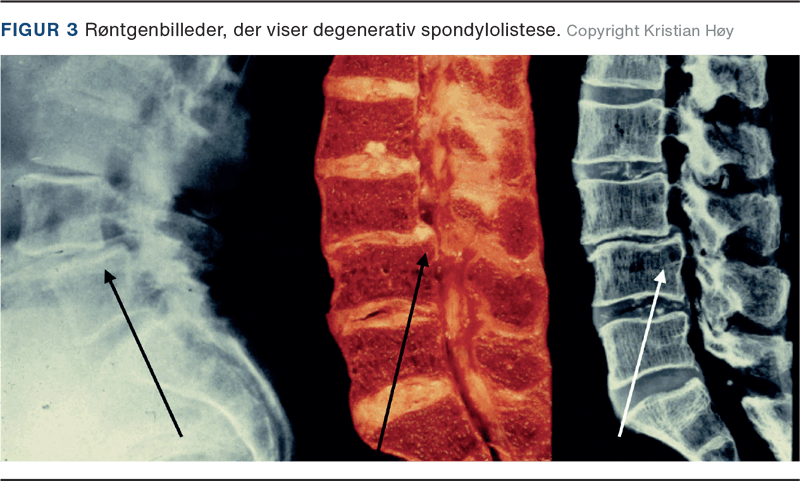

DSL forekommer primært hos ældre over 50 år, og der er en overhyppighed af kvinder [6]. Degeneration af discus medfører instabilitet i facetleddet, hvilket leder til fremadskridning af den kranielle hvirvel – hyppigst ved L4-L5, men tilstanden kan ses i alle degenererede led [7]. Den øgede instabilitet medfører progression i de degenerative forandringer med osteofytformation, ligamenthypertrofi og facetledsartrose i det instabile led, hvilket kan give foraminal- og spinalstenose [8] (Figur 3). Progression af Meyerding ved DSL er således en følge af gradvis discusdegeneration. DSL forekommer i 75% af tilfældene som grad I [8] og leder sjældent til sværere afglidning end grad II, da facetleddene holder hvirvlen på plads i modsætning til ved ISL [9]. I The Copenhagen Osteoartitis Study med 4.151 patienter (heraf 70% kvinder med en gennemsnitsalder på 65 år; gennemsnitsalderen hos mændene var 62 år) forekom DSL med en prævalens på 8,4% hos kvinderne og 2,7% hos mændene. Der er således en høj prævalens og en skæv kønsratio i Danmark. Desuden viste studiet, at BMI, alder og lumbal hyperlordose var risikofaktorer for DSL hos kvinder, mens kun alder var risikofaktor hos mænd [10].